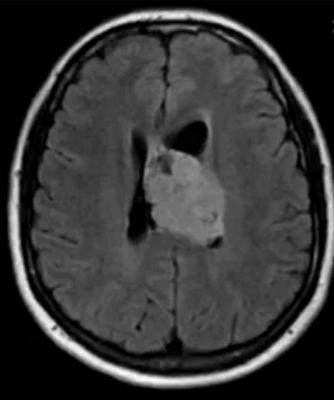

По тому, как выглядит опухоль мозга на МРТ, врачи делают предположения о ее природе. Однозначных утверждений быть не может, так как верификацию образований осуществляют с помощью гистологического анализа. Характерными признаками злокачественных опухолей головного мозга на снимках МРТ являются:

- неправильная их форма;

- нечеткие контуры новообразований;

- выраженный перифокальный отек;

- масс-эффект (смещение близлежащих структур);

- гидроцефалия;

- неоднородное накопление контраста (иногда вообще не накапливают);

- "пестрота" опухоли (кровоизлияния, некрозы и/или кисты в структуре) и др.

- глиобластомы — злокачественные опухоли, которые отличаются высокой скоростью роста и склонностью к инвазии. Выглядят на снимках, как образования неправильной формы, с нечеткими фестончатыми контурами и выраженным перифокальным отеком. Дают выраженный масс-эффект, смещают головной мозг в полости черепа, повреждая его на отдалении от своего местоположения;